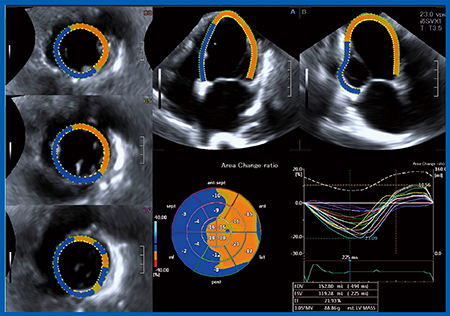

左室の3D-WMTのAuto-tracking Analysisの精度を検証するために,わざと軸をずらした画像で解析を行ったところ,約15秒で自動に画像の軸合わせが訂正され,左室全体の3D Speckle Tracking解析結果が簡便に得られた(図1)。Aplio iシリーズでは,元画像が高画質となったこと,120°×120°のワイドアングルにより拡大心でも心臓全体をとらえられることで,従来よりも解析精度が向上している。さらに,新開発の3Dセクタープローブ(PSI-30VX)が,Artidaで使用していた従来プローブ(PST-25SX)と比較して小型・軽量化され,把持しやすくなったことで操作性が向上したほか,新しい送受信回路で高分解能・高感度を実現するなど,機能が大幅に向上した。

図1 左室の3D-WMTのAuto-tracking解析

対象は健常25例で,3D-WMT を用いてOn-lineのAuto-tracking AnalysisでLVEF,ACR,longitudinal strain,circumferential strainを求めたところ,検者間誤差が小さくきわめて再現性の高い結果が得られ(図2),LVEFとACRのストレイン値の間に非常に良好な相関を認めた。

図2 健常25例における3D-WMTによる左室機能評価